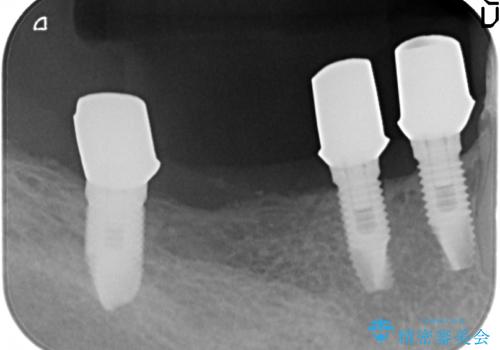

清掃性に優れたジルコニアカスタムアバットメント、ジルコニアクラウンを用いて機能性だけでなく審美性・予知性を高めます。

- 130万円(HAインプラント×3・骨造成・ジルコニアカスタムアバットメント×3・ジルコニアクラウン×4)費用は治療当時の料金となります